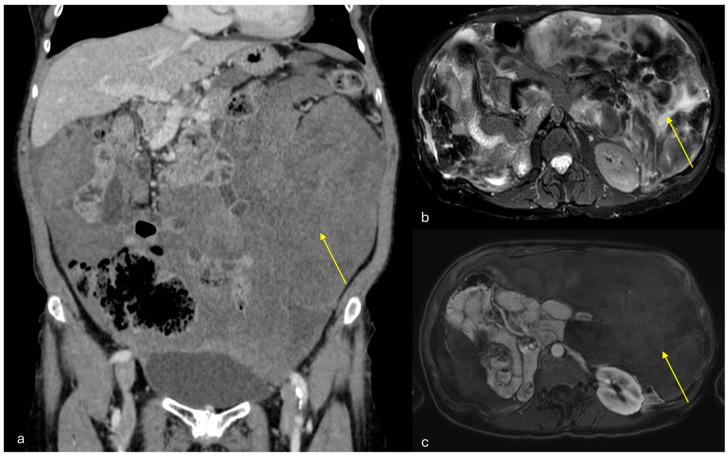

The peritoneum is a thin membrane that lines the abdominal cavity and covers the abdominal organs. It serves as a conduit for the spread of various pathological processes, including gas and fluid collections, inflammation, infections, and neoplastic conditions. Peritoneal carcinomatosis is the most common and well-known pathology involving the peritoneum, typically resulting from the dissemination of gastrointestinal and pelvic malignancies. However, numerous benign and malignant peritoneal diseases can mimic the imaging appearance of peritoneal carcinomatosis. The aim of this review is to revisit the anatomy of peritoneal compartments and elucidate the patterns of peritoneal disease spread. Emphasis is placed on identifying the distinctive imaging features of both neoplastic and non-neoplastic peritoneal diseases that differ from peritoneal carcinomatosis.

腹膜是一层薄的膜,它衬于腹腔内并覆盖腹部器官。它是各种病理过程扩散的通道,包括气体和液体聚集、炎症、感染及肿瘤性疾病。腹膜癌病是涉及腹膜的最常见且广为人知的病理情况,通常由胃肠道和盆腔恶性肿瘤的播散引起。然而,许多良性和恶性腹膜疾病可模仿腹膜癌病的影像学表现。本综述的目的是重新审视腹膜腔室的解剖结构并阐明腹膜疾病的扩散模式。重点在于识别与腹膜癌病不同的肿瘤性和非肿瘤性腹膜疾病的独特影像学特征。